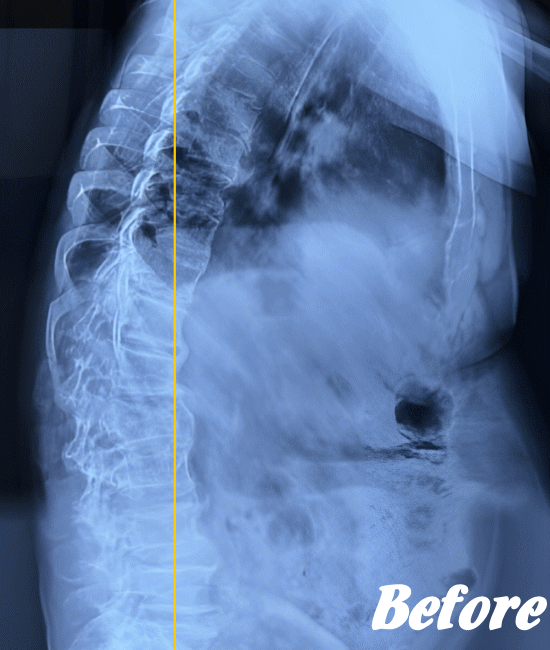

身体に無理をかけず骨や関節の位置を解剖学的に正しい位置へ調整することで、痛みを取り除いていきます。慢性化した痛みも改善します。

多くの場合、頸椎(首の骨)、肩甲骨、背中の胸椎(背骨)、肋骨、そして骨盤(仙腸関節)を調整すれば、痛みは早い段階でなくなり、健康な状態に回復します。